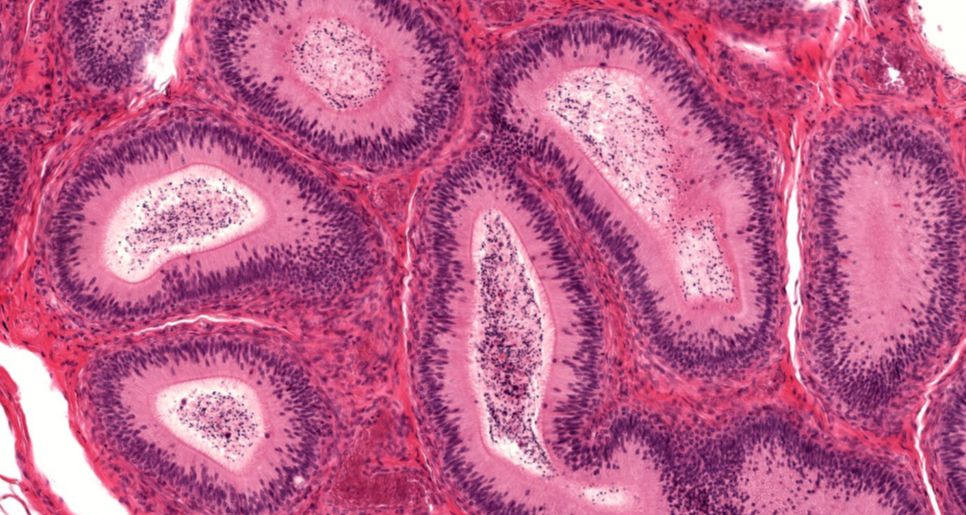

Epidídimo

Epidídimo - Epitélio pseudo estratificado